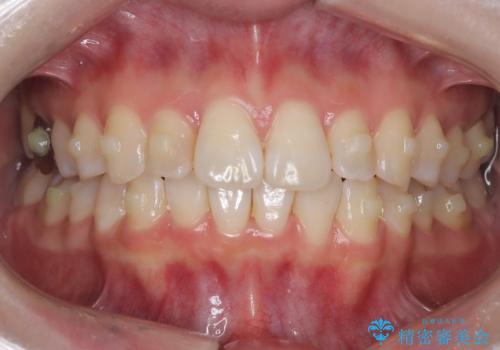

前歯のガタつきをマウスピース矯正で改善

- 前歯のガタツキが気になると来院されました。

マウスピース矯正治療を選択しました。

奥歯の噛み合わせは綺麗に噛んでいたため、前歯の叢生(でこぼこ)に集中して治療するように計画しました。